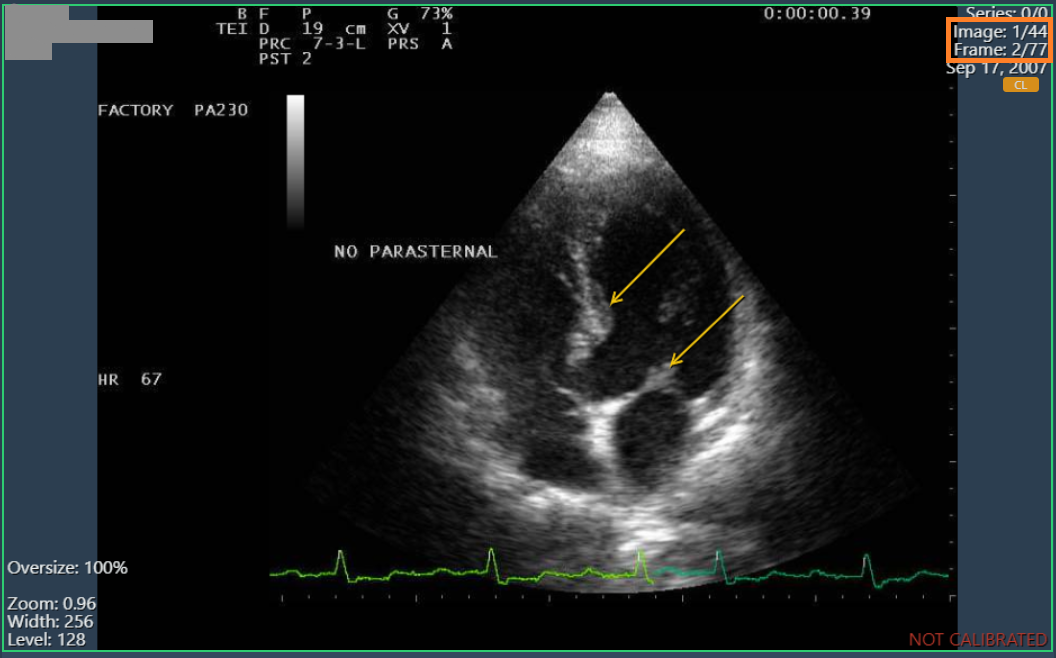

Annotations on multiframe images

Annotations on multi-frame images were not enabled independently, so they were applied to all frames of an image. Now annotations can be made and displayed on each frame as expected.

Annotations in frame 2/77

Annotations in frame 3/77